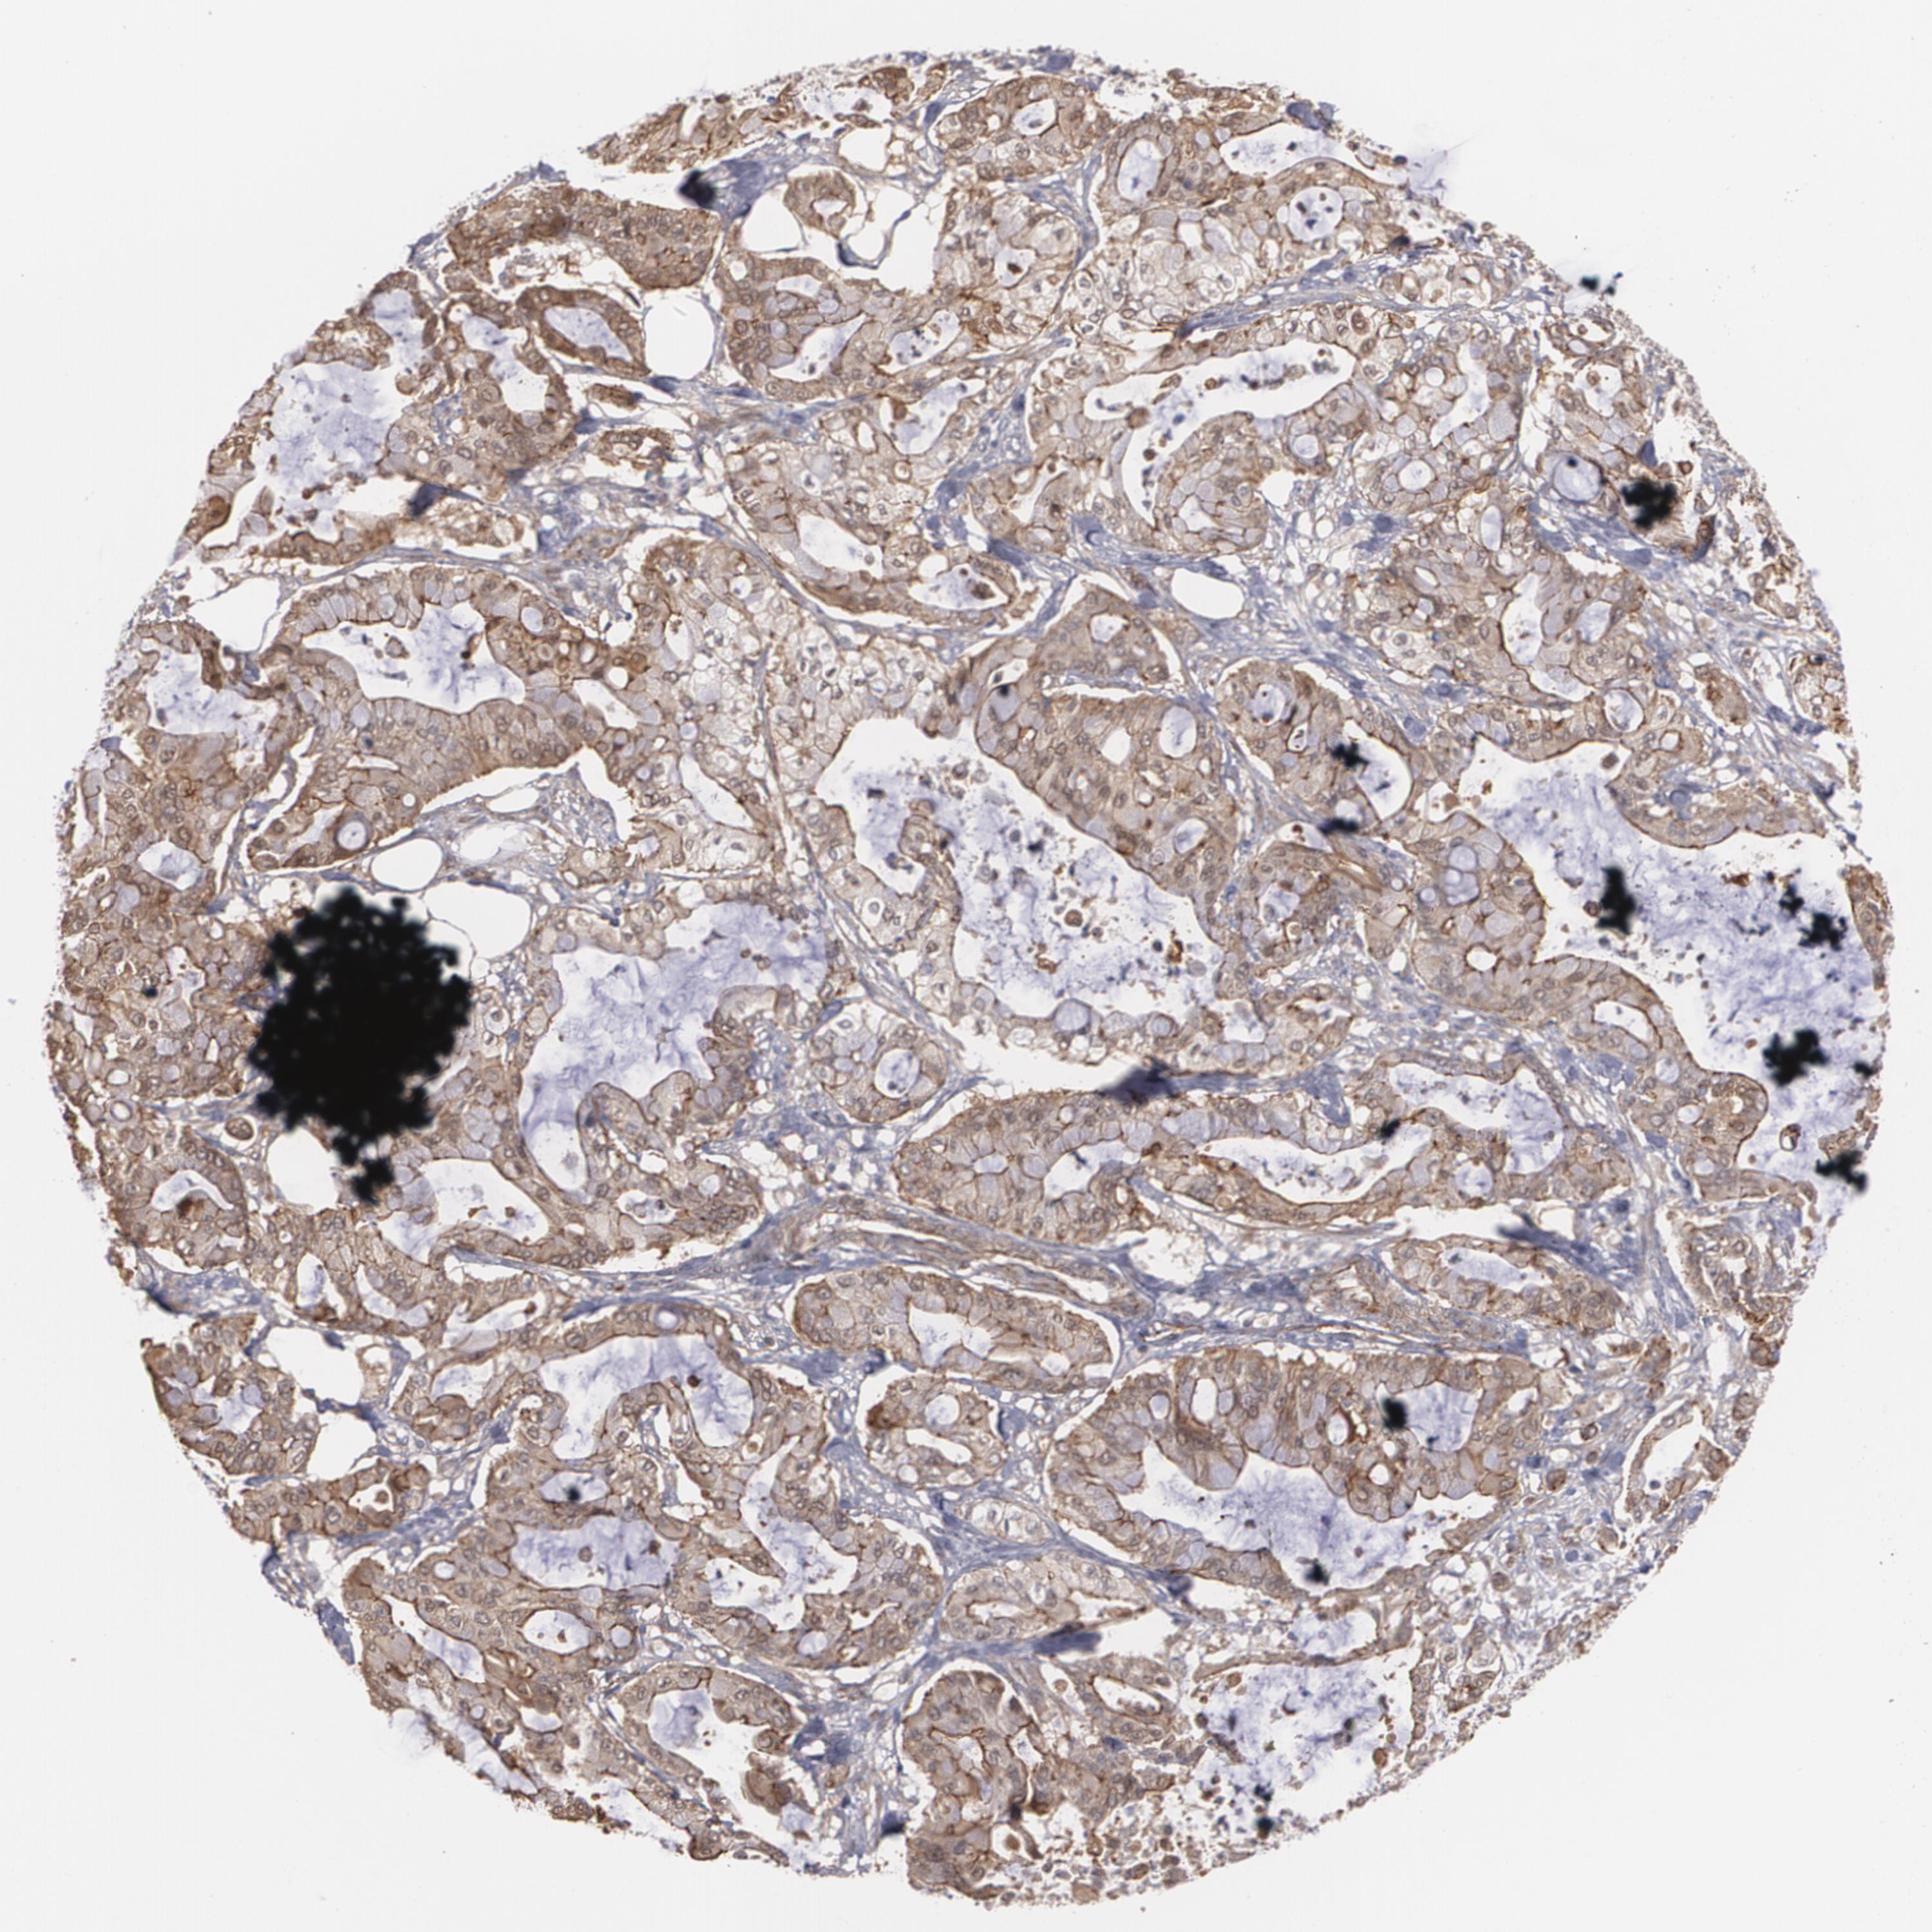

PANCREATIC CANCER - Protein expressioni

A mouse-over function shows sample information and annotation data. Click on an image to view it in a full screen mode. Samples can be filtered based on level of antibody staining by selecting one or several of the following categories: high, medium, low and not detected. The assay and annotation is described here.

Note that samples used for immunohistochemistry by the Human Protein Atlas do not correspond to samples in the TCGA dataset.

Antibody stainingi

Antibody staining in the annotated cell types in the current human tissue is reported as not detected, low, medium, or high, based on conventional immunohistochemistry profiling in selected tissues. This score is based on the combination of the staining intensity and fraction of stained cells.

Each image is clickable and will lead to virtual microscopy that enables deeper exploration of all samples and also displays staining intensity scores, fraction scores and subcellular localization as well as patient and tissue information for each sample.

Antibody HPA001636

Antibody HPA001637

Antibody CAB010822

Adenocarcinoma, NOS

Adenocarcinoma, metastatic, NOS